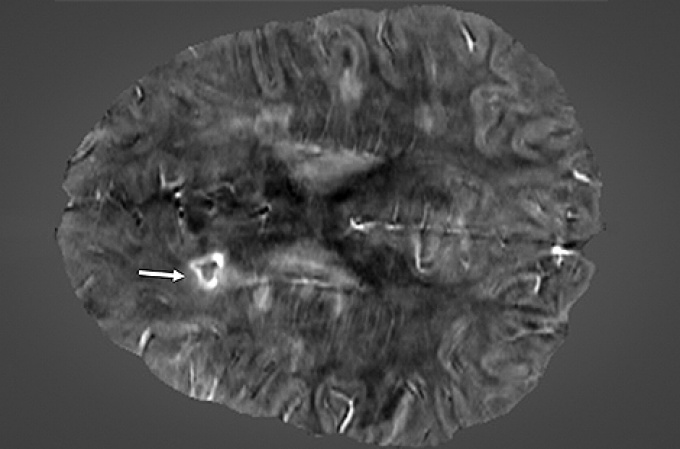

An image of the brain of a 45-year-old female with secondary-progressive MS that has a paramagnetic rim lesion.

This image of the brain of a 45-year-old female with secondary-progressive MS indicates with a white arrow the presence of a paramagnetic rim lesion. The image was obtained using Quantitative Susceptibility Mapping (QSM), an advanced MRI technique that can detect these lesions.

One of the new criteria described is magnetic resonance imaging (MRI) markers in the brain called paramagnetic rim lesions, which have been extensively studied by UB researchers.

The new diagnostic criteria are designed to change that with the inclusion of additional diagnostic markers that allow confirmation of MS in a single visit. Two can be identified by MRI: the central vein sign, where a blood vessel is seen running directly through the center of an MS lesion in the brain, and paramagnetic rim lesions, or PRLs.

Last year, the UB researchers published the first longitudinal studies of MS patients done over five- and 10-year periods, linking these PRLs to MS. They were able to do it with the advent of new, iron-sensitive neuroimaging techniques. The UB researchers found that PRLs may be a better indicator of brain inflammation in MS than the white matter lesions that had traditionally been seen as the primary indicator of disease progression.

“Paramagnetic rim lesions are highly specific to MS and represent ongoing damage in the brain,” says Dwyer. “While not everyone who has MS will have them, these lesions are extremely rare in other diseases — so if we see them in someone, we can be much more confident that that person has MS.”